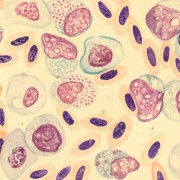

Illustrations and documents

Lilly Ebstein Lowenstein (1897-1966) led a life between science and art, drawing and taking photographs in the fields of Medicine and Zoology. In her work, Lilly combined her technical knowledge of photography and drawing, the study of the sciences and a remarkable talent for aesthetics. She was born in Germany and studied at the Lette-Verein School in Berlin from 1911 to 1914. In 1925, she immigrated with her husband and two children to São Paulo. In 1926, she became an illustrator and photomicrographer at the Illustration and Photography Department at the School of Medicine (USP, as of 1934), which she headed for thirty years after 1932. Lilly collaborated at Instituto Biológico de Defesa Agrícola e Animal (the Biological Institute for the Defense of Agriculture and Animals), from 1930 to 1935, namely in the Avian Pathology Department. A life with art dedicated to the research and dissemination of science.